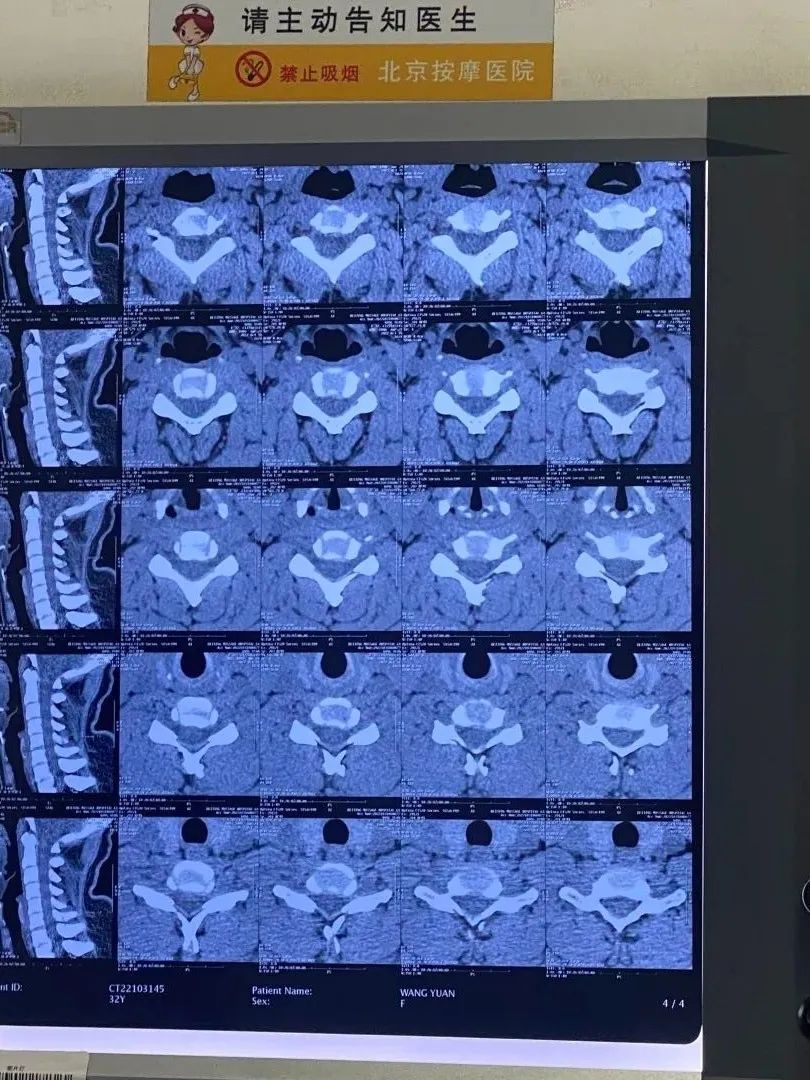

一个变直的颈椎CT

看看你的颈椎到哪个阶段了